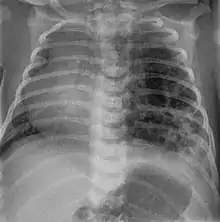

Congenital pulmonary airway malformation

Congenital pulmonary airway malformation (CPAM), formerly known as congenital cystic adenomatoid malformation (CCAM), is a congenital disorder of the lung similar to bronchopulmonary sequestration. In CPAM, usually an entire lobe of lung is replaced by a non-working cystic piece of abnormal lung tissue. This abnormal tissue will never function as normal lung tissue. The underlying cause for CPAM is unknown. It occurs in approximately 1 in every 30,000 pregnancies.[1]